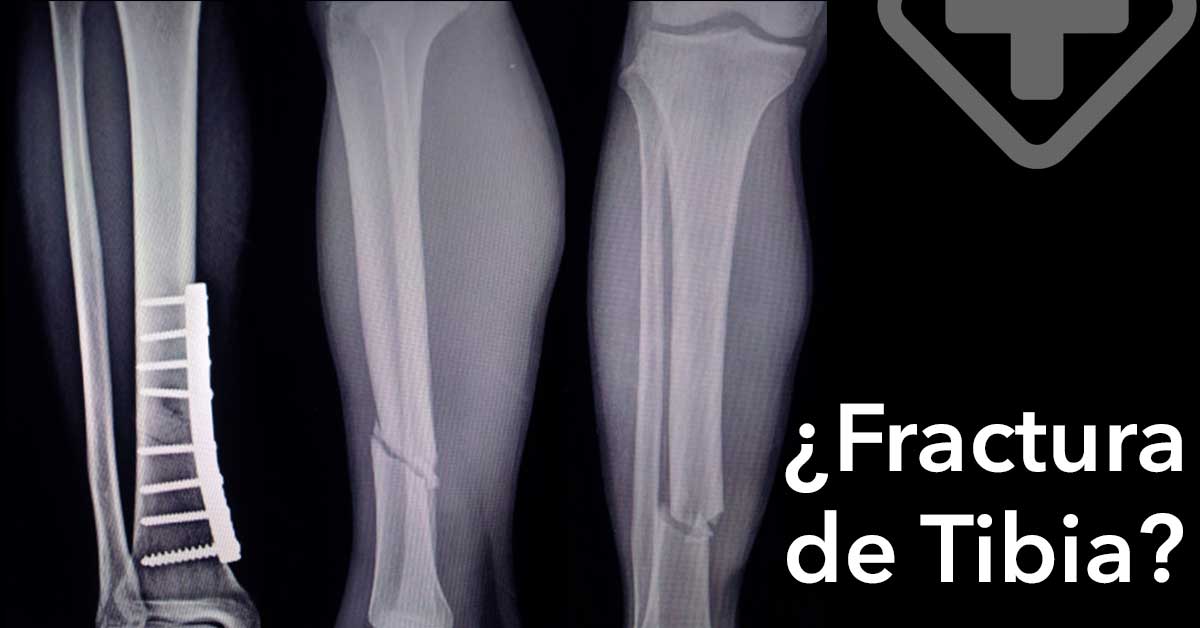

La tibia es el hueso largo localizado en la parte baja de la pierna entre la rodilla y el pié. Las fracturas de tibia son comunes y usualmente son causadas por una lesión, o por ejercer presión continua sobre el hueso.

Fractura significa “ruptura”. En algunos casos, el único síntoma de una pequeña fractura es dolor en la espinilla al caminar. En casos más severos, el hueso de la tibia puede sobresalir a través de la piel.

Para diagnosticar una fractura de tibia, el médico preguntará sobre tu historial médico y cómo ocurrió la lesión. Llevará a cabo una examinación y pedirá realizar alguna de las siguientes pruebas: